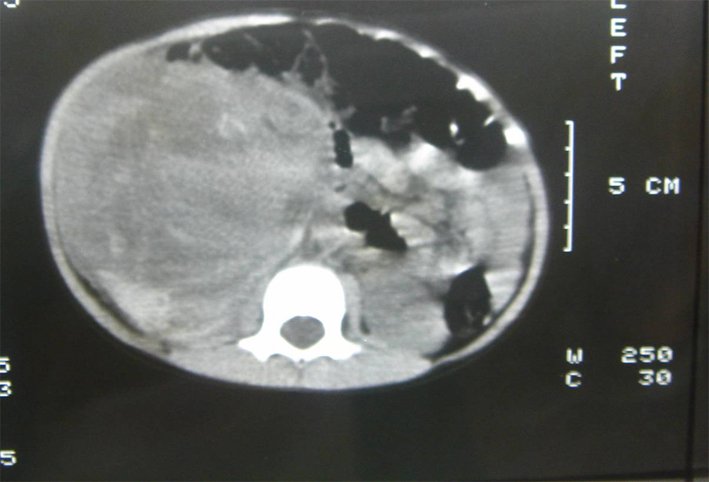

Case 2: A 10-year-old, female, presented with abdominal pain after falling from the couch. A CT was performed and showed a large hematoma / tumor in the right upper renal pole, with calcifications (Figure-2). No renal injury was observed. She was initially treated conservatively for renal trauma in a different hospital, but due disparate size of the CT findings and mechanism of trauma and renal calcifications, she was refered to our institution. Laparotomy was performed, revealing a ruptured right upper pole tumor. Nefrectomy and surgical staging were undertaken. Pathology showed blastematous Wilms tumor. Patient refused further treatment, as stage III and returned two years later with pulmonary metastasis. She underwent chemo and radiotherapy, as well as thoracotomy. Patient is alive, three years disease-free after the end of treatment.

Figure 2 - CT of case 2: renal mass due to Wilms tumor with hemorrhage and calcifications.